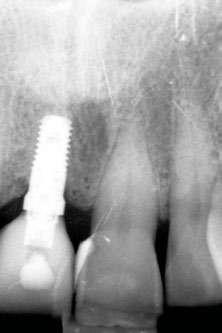

laterales se ponen de manifiesto aún más varias lesiones de esmalte que indican la parafunción en el paciente, unido a los desgastes excesivos en varias zonas (figuras 3 y 4). El paciente acude por dolor y movilidad en la pieza 11, que se ha incrementado en los últimos días, además de sensación de “diente crecido” que como podemos ver en las fotografías iniciales es real, ya que el diente se encuentra ligeramente extruido en relación con el contralateral. Estos signos parecen indicarnos una fractura o fisura. En la fotografía oclusal, podemos observar el desplazamiento del diente debido a la movilidad (figura 5). Posteriormente se realiza un sondaje positivo de la pieza, que lleva a 11 mm por lo que se confirma la sospecha de fractura y se procede a la exodoncia del diente, realizándose una regeneración posterior del alveolo con PRGF-Endoret y

esperándose 4 semanas hasta el cierre de los tejidos blandos y la neoformación ósea inicial para la colocación de un implante temprano. Cuatro semanas después, realizamos un cone-beam de control para conocer el estado del tejido óseo y poder planificar el implante. En el corte seccional observamos que se ha regenerado por completo el lecho receptor y tenemos un hueso óptimo para la inserción del implante, que por el tiempo transcurrido además es muy sencillo de expandir, con el propio implante generándose una expansión atraumática que nos permitirá ganar anchura ósea y con un implante estrecho de 3,5 mm de diámetro logramos posicionarlo sin dañar la desembocadura del nervio incisivo (figura 6). En cuanto a la longitud, con 7,5 es suficiente, no necesitándose un tamaño mayor para un correcto rendimiento biomecánico posterior.

Figura 6. Corte seccional de planificación del implante donde observamos el volumen óseo regenerado y la disposición del implante que se va a insertar por delante de la desembocadura del nervio incisivo.

El paciente continúa en seguimiento posterior, con revisiones cada 6 meses durante los dos primeros años. En todas ellas no existe complicación ni pérdida ósea asociada al implante, tal como podemos ver en la radiografía de control a los dos años (figura 18).

Figura 17. Radiografía tras la colocación de la prótesis definitiva.

Figura 18. Radiografía de control a los dos años, donde observamos el implante y la estabilidad del tratamiento.

Cinco años después, llevamos a cabo un nuevo cone-beam y en el podemos observar la evolución del implante y de la sobre-corrección vestibular llevada a cabo en la cirugía inicial. Tanto el implante como el hueso que se ha formado a nivel vestibular fruto del injerto empleado está estable y se mantiene sin pérdida ósea asociada, tal como mostramos en los cortes del cone-beam

inicial y final a los 5 años de seguimiento (figura 19). En las imágenes intraorales tomadas en este punto del seguimiento se constata el éxito del tratamiento (figuras 20 y 21). En la radiografía periapical, observamos con mayor detalle la regeneración del tejido óseo del diente en posición 11 así como la estabilidad ósea del implante (figuras 22 y 23).

Figuras 22 y 23. Radiografía periapical inicial y a los 5 años de seguimiento.